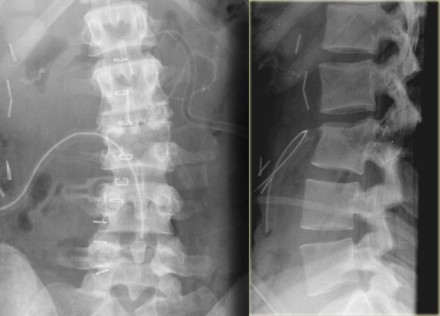

On the left images of a 21-year-old female who presented after sustaining a seatbelt type injury.

She had an exploratory laparotomy for repair of a ruptured duodenum.

There was no neurologic deficit.

What we see is a classic example of a chance fracture, which is a three column injury with a horizontal orientation of the fracture.

What is unique about the Chance fracture is the horizontal orientation, which is nicely demonstrated on the sagittal reconstructions on the left.

Also on the coronal reconstructions we can see the horizontal orientation of the fracture.